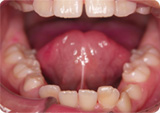

左は正常な上唇小帯です。右は上唇小帯の低位付着が認められます。

低位付着のため前歯の間に小帯が入り込み隙間ができます。

小帯を治しておかないと、矯正治療で隙間を閉じてもまた開いてくる原因になり ます。